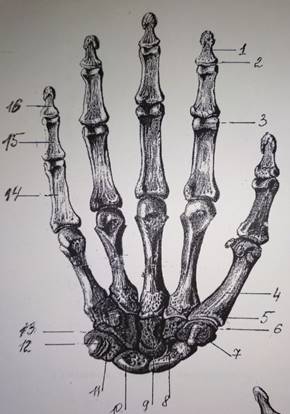

Анатомия кисти руки и строение костей